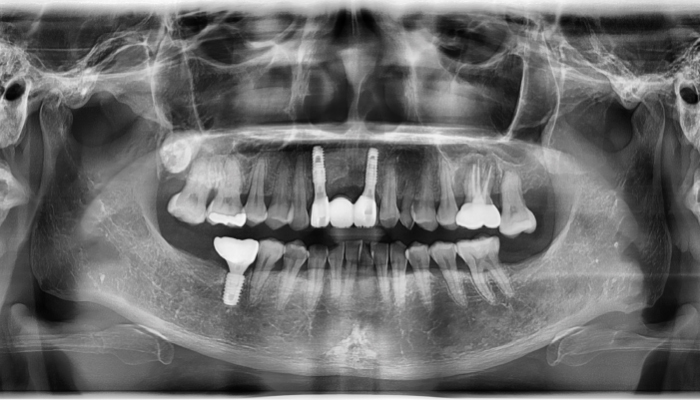

상악동거상술 수술사진

상악동거상술 전후 사례

• 식립 전

식립 후

• 식립전

식립후